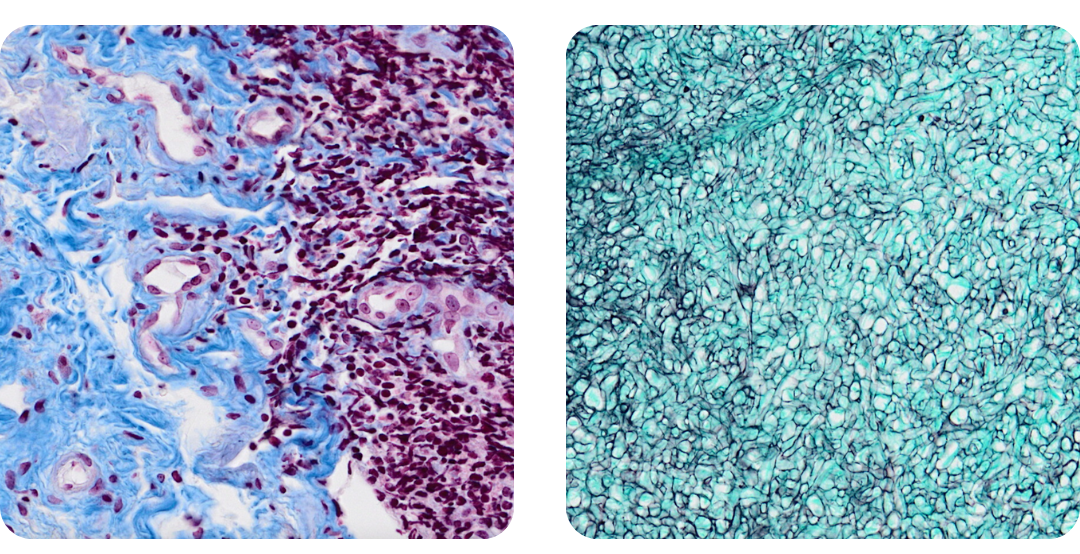

- Connected-Pathology’s advanced histopathology and digital pathology services, expanding its scope into multi-species and translational studies

- Deliver high-throughput histopathology services including IHC, IF, ISH, and AI-supported image and biomarker analysis across multiple study types